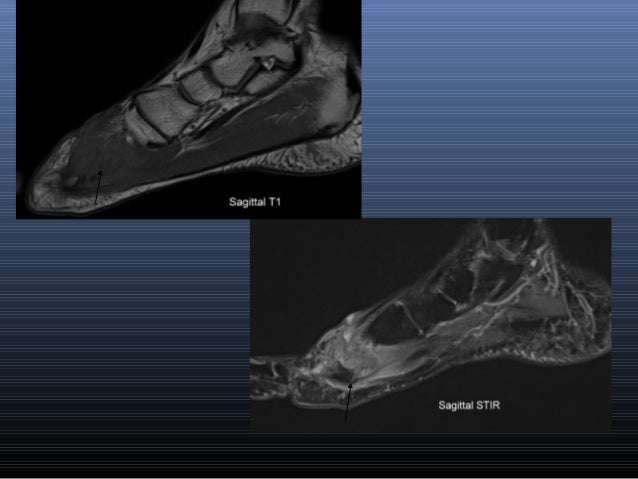

Plantar Fibroma and Fibromatosis | Mr Malik at LFAC from lfaclinic.co.uk Learn more details about them at kenhub! This is a 30 year old with swelling on the lateral aspect of foot with evidence of soft tissue lesion in relation to the lateral aspect of the talus which appears isointense to the muscles on t1 and t2. Start studying mri procedures foot/ankle review. Mri with hardware in foot? Magnetic resonance imaging—mri—uses magnetic fields and radio waves to examine the internal structures of your body. Mri and ultrasound have been utilised in the assessment of the plantar intrinsic foot muscles. Shop our pre workout and nitric oxide supplements. Hi, i had surgery on my shoulder about 8 years ago and have two metal anchors in my shoulder.

Head, neck, arm, foot, pelvis, etc. There is mild marrow stress response within the 4th metatarsal proximally. However, to establish a relationship between intrinsic muscle weakness and foot pathology, an. Near normal foot mri for reference. Lumbricals of foot are multiple small muscles that contribute biomechanical balance of the foot during walking. Learn about foot and ankle mri here. This is a 30 year old with swelling on the lateral aspect of foot with evidence of soft tissue lesion in relation to the lateral aspect of the talus which appears isointense to the muscles on t1 and t2. Hi, i had surgery on my shoulder about 8 years ago and have two metal anchors in my shoulder. Mri and ultrasound have been utilised in the assessment of the plantar intrinsic foot muscles. Related online courses on physioplus. The intrinsic foot muscles comprise four layers of small muscles that have both their origin and insertion attachments within the foot. Abdm, abductor digiti minimi muscle; Shop our pre workout and nitric oxide supplements.